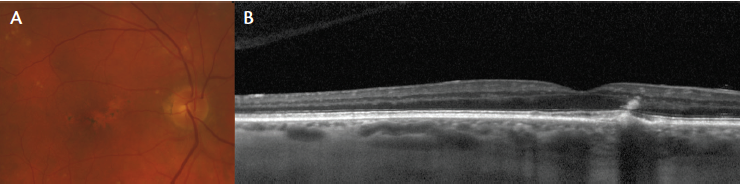

Figure 6. PPE in an 85-year-old man showing reduced fundus tessellation related to the presence of a thick choroid (A). Focal RPE changes are seen on the OCT scan (B).

REDUCED FUNDUS TESSELLATION

In addition to the multimodal imaging features described above, eyes with pachychoroid spectrum disease typically exhibit reduced fundus tessellation at the posterior pole when examined clinically or with color or red-free photography. The reason for reduced visualization of choroidal features through the RPE may be due to changes in choroidal pigmentation or to choroidal thickening. However, where the inner choroid is attenuated and the pachyvessels course along the outer aspect of the Bruch membrane, they may be visualized directly or they may incite RPE hyperplasia. Recognition of these features can raise a clinician’s suspicion for a pachychoroid-related diagnosis (Figure 6).11